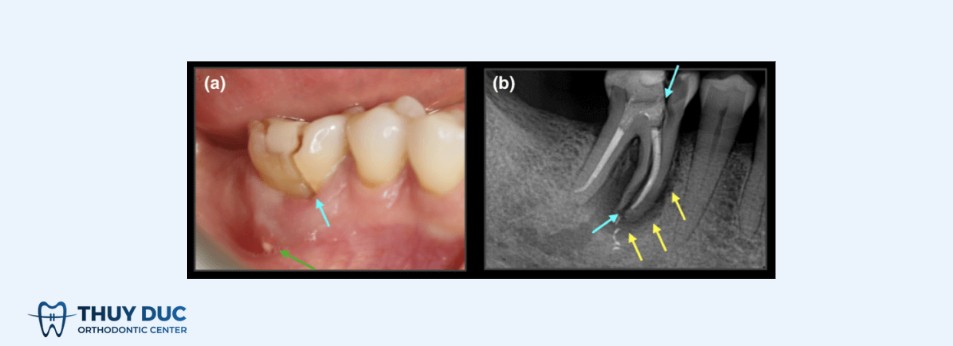

Trường hợp 3: Vỡ dọc lan xuống chân răng, mức độ nghiêm trọng

Đặc điểm:

- Đau rõ khi nhai, đặc biệt là khi thả lực cắn.

- Nướu sưng khu trú, có thể xuất hiện lỗ rò mủ.

- Răng lung lay mức độ khác nhau.

- Phim X-quang hoặc CT Cone Beam cho thấy tiêu xương dọc theo chân răng hoặc hình ảnh viêm quanh chóp không điển hình.